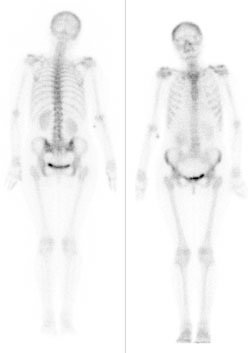

Który narząd został uwidoczniony na przedstawionym obrazie scyntygraficznym?

A. Wątroba.

B. Płuca.

C. Trzustka.

D. Serce.

Zamieszczone na ilustracji obrazy dotyczą badania

A. dopplerowskiego.

B. audiometrycznego.

C. scyntygraficznego.

D. densytometrycznego.